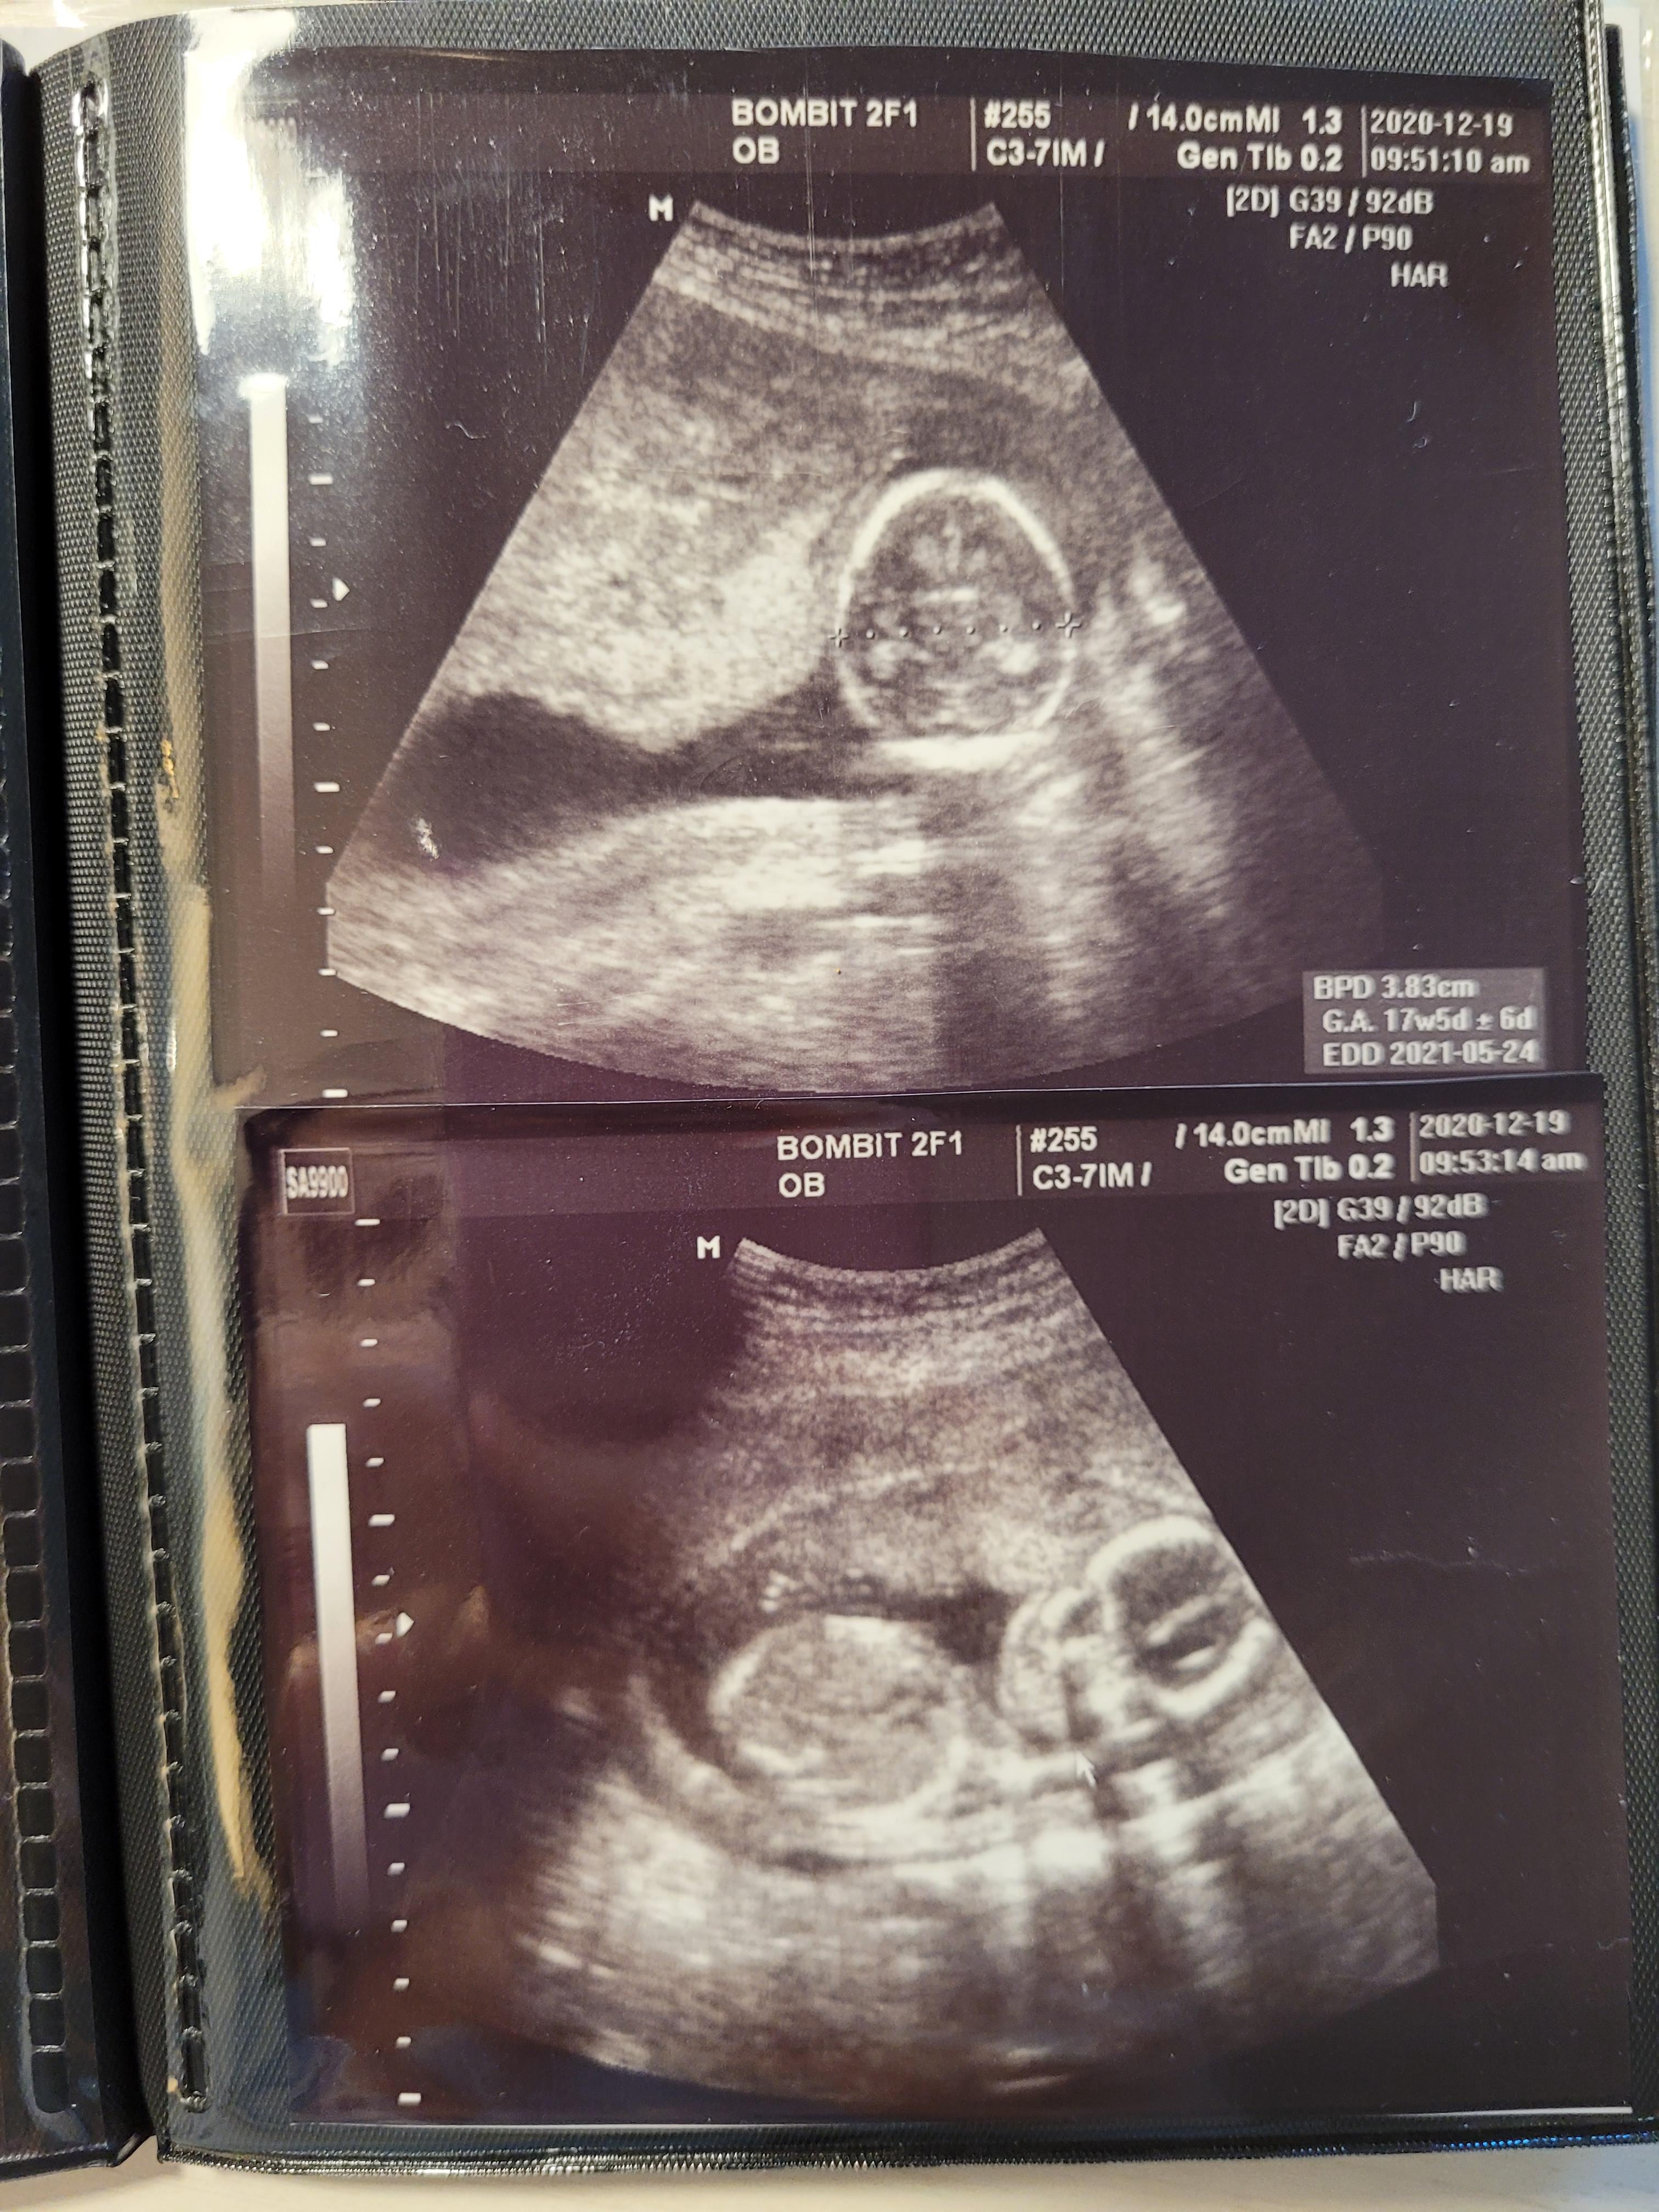

초음파로 태아 상태부터 확인합니다.

16주 0일인데, 17주 5일 크기까지 커버린 우리 행복이 ㅎㅎ

쑥쑥 잘 자라주고있어요

배둘레, 머리둘레 모두 주수보다 잘 자라주어서 뿌듯했어요

아무 이상도 없고 건강하게 잘 크고있네요^^